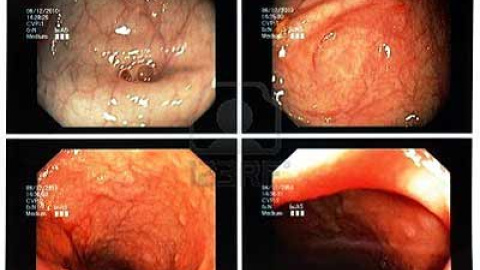

La colonoscopia es la prueba que diagnostica con total precisión el cáncer de colon y ayuda a su prevención. Según el Dr. Gonzalo Guerra Flecha, fundador del Centro Médico-Quirúrgico de Enfermedades Digestivas, "la colonoscopia es la herramienta más precisa para revenir el cáncer de colon. El motivo es que permite una visión completa del colon y de sus osibles patologías, como son los pólipos. Los pólipos son tumores (benignos o malignos) que se forman en la mucosa del colon y que, en muchos casos, son los precursores de un cáncer de colon. Si éstos se extirpan durante la colonoscopia el riesgo de sufrir un cáncer de colon en el futuro disminuye de manera significativa".

La colonoscopia no es la única prueba que ayuda a realizar un diagnóstico precoz de esta enfermedad. Existen otras pruebas menos invasivas y que ayudan a los especialistas de aparato digestivo a hacer cribados a la población de riesgo, compuesta por personas mayores de 50 años, personas con antecedentes familiares de la enfermedad, pacientes que han desarrollado pólipos en el intestino grueso con anterioridad y pacientes con Enfermedad de Crohn o colitis ulcerosa. La colonoscopia virtual es una alternativa menos invasiva y que permite a los astroenterólogos una visión en tres dimensiones de la morfología del colon y, por tanto, detectar cualquier anormalidad que pueda indicar un principio de enfermedad. El test septina 9 es una novedosa técnica diagnóstica que permite detectar con un sencillo análisis de sangre la resencia de un marcador tumoral que se encuentra en el 90% de los casos de cáncer de colon.